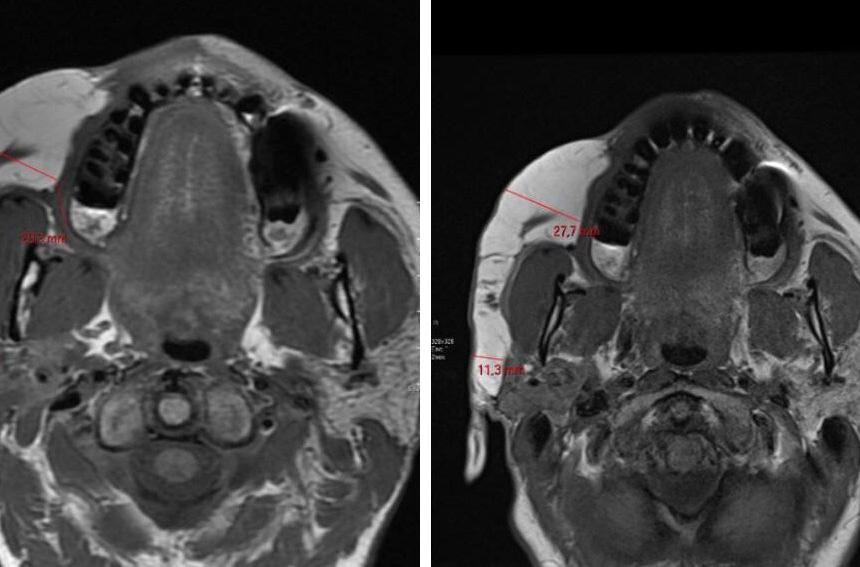

Tratamento da síndrome de Parry-Romberg e da esclerodermia linear em golpe de sabre, com aplicação do ácido

76 poli-L-láctico (PLLA): avaliação da resposta clínica e ultrassonográfica de alta resolução

Renato Roberto Liberato Rostey, Cristiane Ferreira Rallo de Almeida, Danilo Olavarria D’Aquino, Caio Leal Carvalho